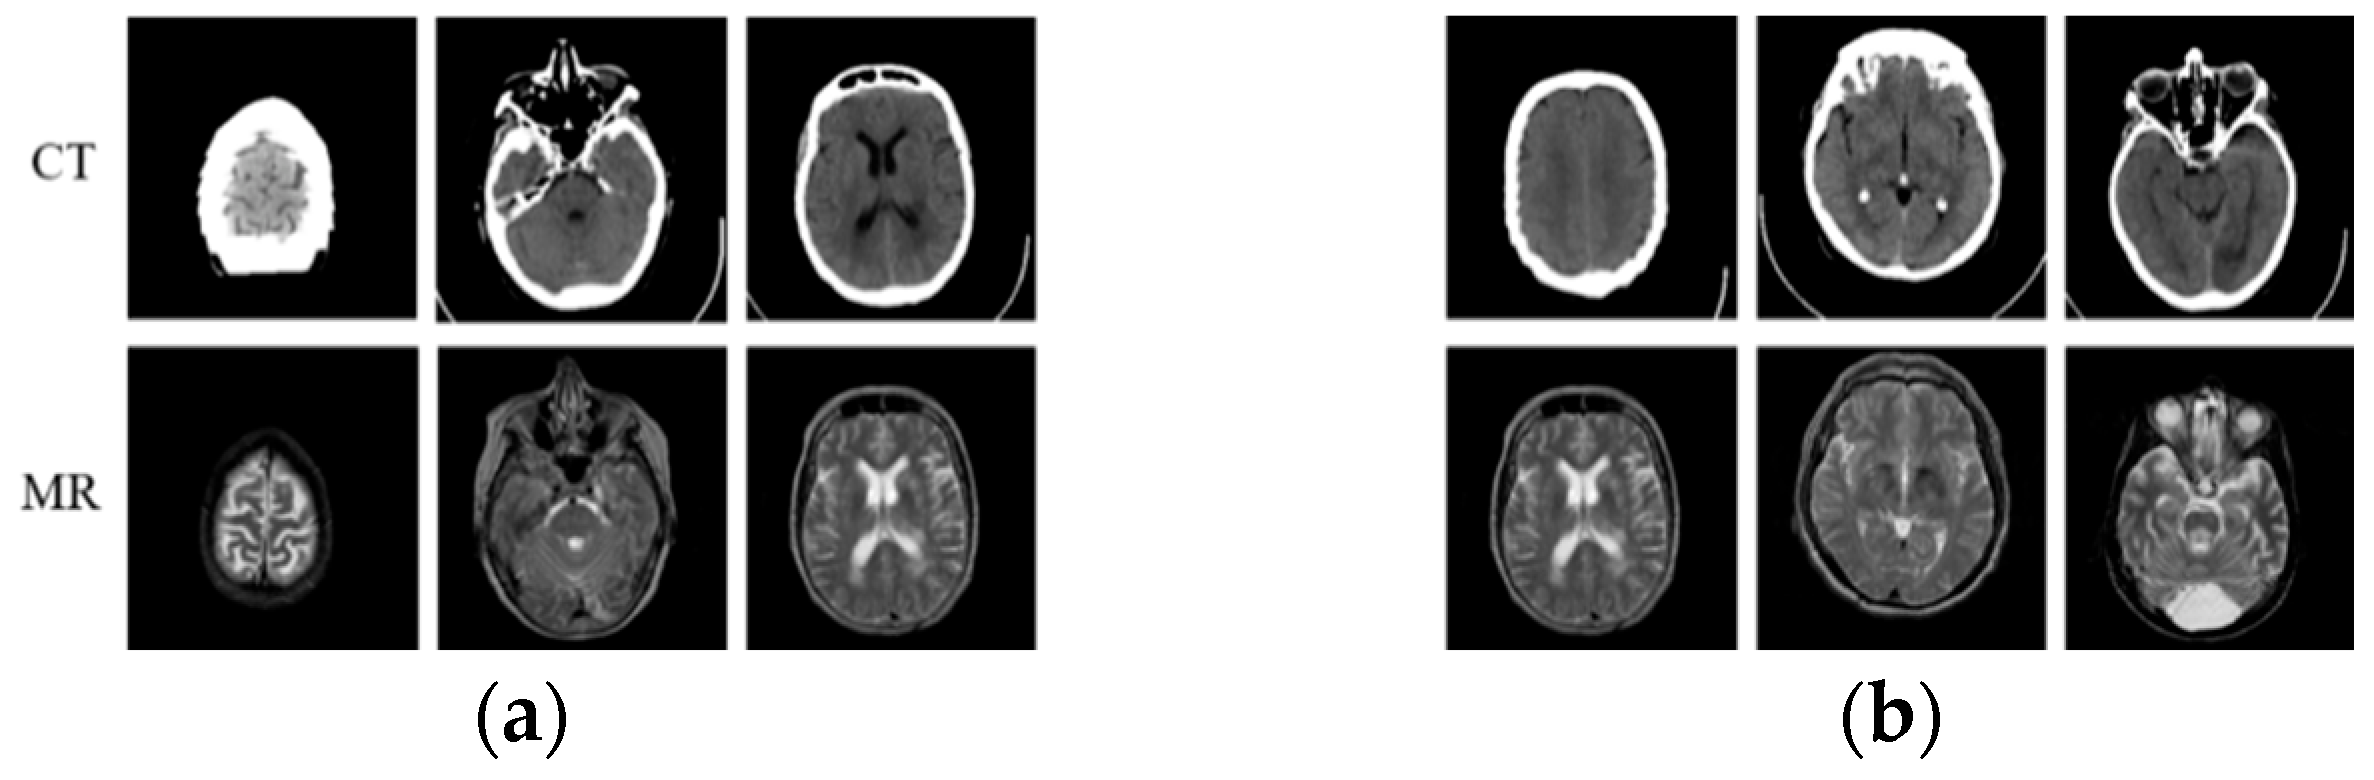

4.2. Comparison of Results under Different Objective Optimization Functions

4.3. Comparison of Results under Different GAN Models